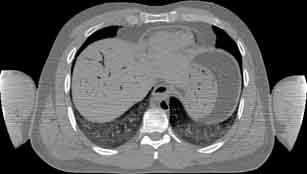

Visible Human male: Sectio transversalis 1482

CT

NMR

Pd                          / T2 \                         T1